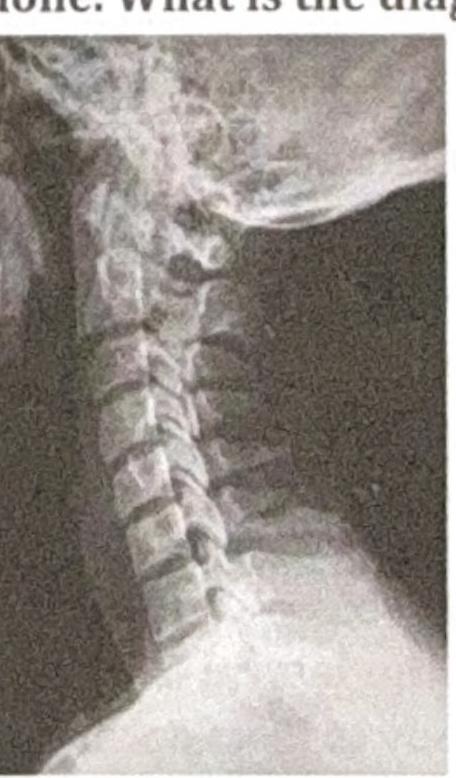

A man presents with back pain following a road traffic accident (RTA). There is no history of neurological deficit. An X-ray of the spine is done. What is the diagnosis based on the image?

Explanation: ***Spinous process fracture*** - The X-ray image reveals a **fracture of the spinous process** of one of the cervical vertebrae, characterized by a visible discontinuity or separation of this posterior bony projection. - This type of fracture, often caused by direct trauma or forceful hyperextension/hyperflexion, typically presents with localized back pain but often **without neurological deficit** as the spinal canal generally remains intact. *Chance fracture* - A **Chance fracture** (or seatbelt fracture) is a horizontal fracture of a vertebral body, usually in the thoracolumbar region, often caused by distractional forces (e.g., flexion over a seatbelt). - It involves all three columns of the spine (anterior, middle, and posterior) and is not seen in the cervical spine X-ray provided. *Compression fracture* - A **compression fracture** is characterized by the collapse of the vertebral body, often resulting in a wedge shape. - This typically appears as reduced height of the anterior vertebral body on an X-ray, which is not the primary finding in the image. *Fracture of base of vertebrae* - A **fracture at the base of the vertebrae** is a non-specific term; specific vertebral fractures are categorized based on the part of the vertebra affected (e.g., vertebral body, pedicle, lamina, spinous process). - The image distinctly shows a fracture in the **spinous process**, not the main body or base of the vertebra.